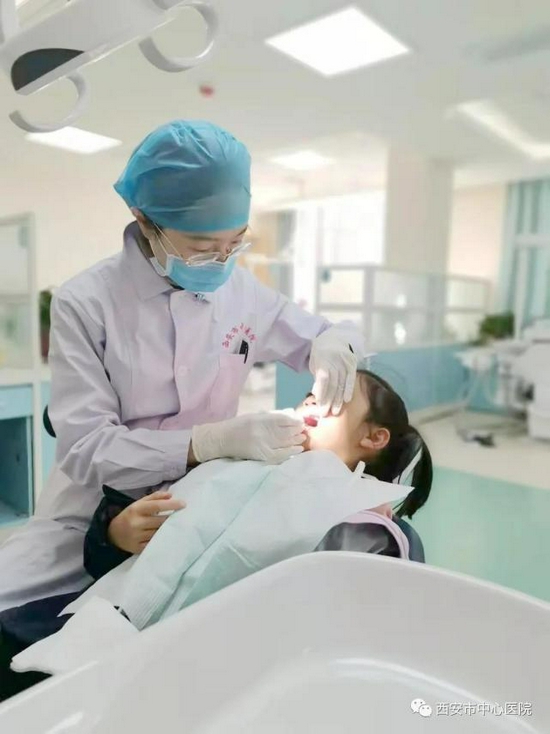

西安市中心医院开启2021年度免费窝沟封闭服务 为预防儿童后牙窝沟龋提供有效保障

既然是国家免费工程,那么这个羊毛该什么时候薅,怎么薅呢?因为是针对7-9岁儿童六龄齿的窝沟封闭,所以在孩子到小学二年级的时候,学校会给每个孩子下发《窝沟封闭知情同意书》,西安市的各个小学均有自己的定点医院提供免费的窝沟封闭服务。请家长在收到同意书后,根据上面的联系电话进行预约登记,并在预约登记的时间带着孩子以及填好知情同意书准时前往定点医院进行窝沟封闭,整个过程没有任何费用。西安市中心医院口腔科为辖区内新知小学、育英小学及后宰门小学三所学校的定点医院,并已于近期开始了2021年度的窝沟封闭工作。我们有专门的窝沟封闭团队为定点学校的孩子们提供优质的窝沟封闭服务。